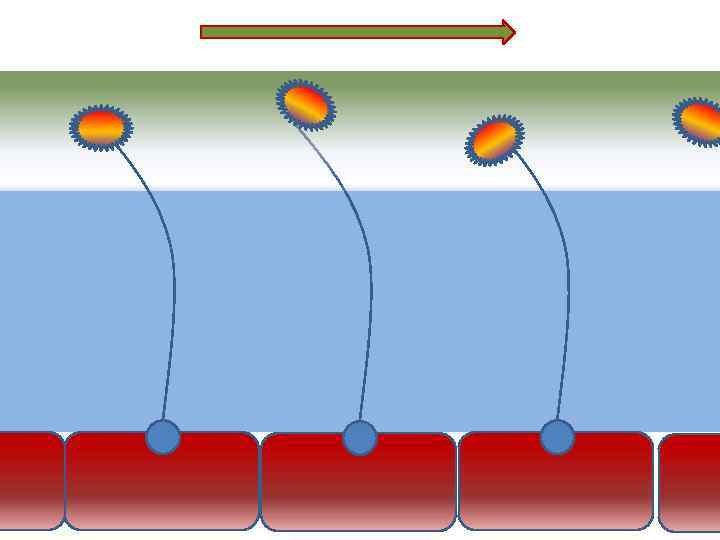

Оптимальное увлажнение Достаточная продукция слизи Хороший транспорт Экономит энергию и воду Защитная функция

Оптимальное увлажнение Достаточная продукция слизи Хороший транспорт Экономит энергию и воду Защитная функция

Механизм защиты легкого Слизь (зеленый цвет) нейтрализует и связывает патогенную флору(синий цвет) Слизь – это барьер между клетками и патогенной флорой Слизь – это транспортное средство

Механизм защиты легкого Слизь (зеленый цвет) нейтрализует и связывает патогенную флору(синий цвет) Слизь – это барьер между клетками и патогенной флорой Слизь – это транспортное средство

Нормальное состояние слизистого бронхиального секрета возможно только при 100% относительной влажности воздуха

Нормальное состояние слизистого бронхиального секрета возможно только при 100% относительной влажности воздуха

Факторы риска Недостаточное увлажнение дыхательной смеси Высушивание трахеи и бронхов

Факторы риска Недостаточное увлажнение дыхательной смеси Высушивание трахеи и бронхов

Плохое увлажнение • Вязкая слизь - потеря ресничек • Высушивание слизистой смерть клеток • Высушивание слизи в бронхиолах-ателектазы • Затраты энергии на согревание воздуха • Затраты воды на увлажнение

Плохое увлажнение • Вязкая слизь - потеря ресничек • Высушивание слизистой смерть клеток • Высушивание слизи в бронхиолах-ателектазы • Затраты энергии на согревание воздуха • Затраты воды на увлажнение

44 мг/л 37°С 30 мг/л и < <

44 мг/л 37°С 30 мг/л и < <